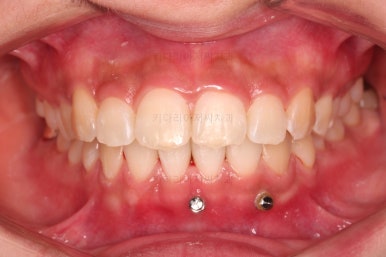

우선 윗니 앞니는 장치를 부착했고요.

아래 앞니는 장치 부착 이전에 아래로 앞니를 내려줄 미니스크류를 식립했습니다.

미니스크류가 단단하게 붙었을 시점에 아래 앞니도 장치를 부착하고요.

과개교합 개선을 위해서 미니스크류까지 힘을 줘서 아래 앞니를 내려줍니다.

아래 앞니는 브라켓보다는 훨씬 작은 미니튜브 장치를 사용했습니다.

과개교합의 경우 브라켓을 부착하게 되면 씹히게 되어 치료과정이 수월하지 못하기 때문이죠.

장치 부착 시점의 장치가 보이는 모습과 입매 변화 관찰해 주시고요.